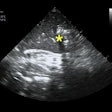

TEE is 'invaluable tool' for patients with COVID-19